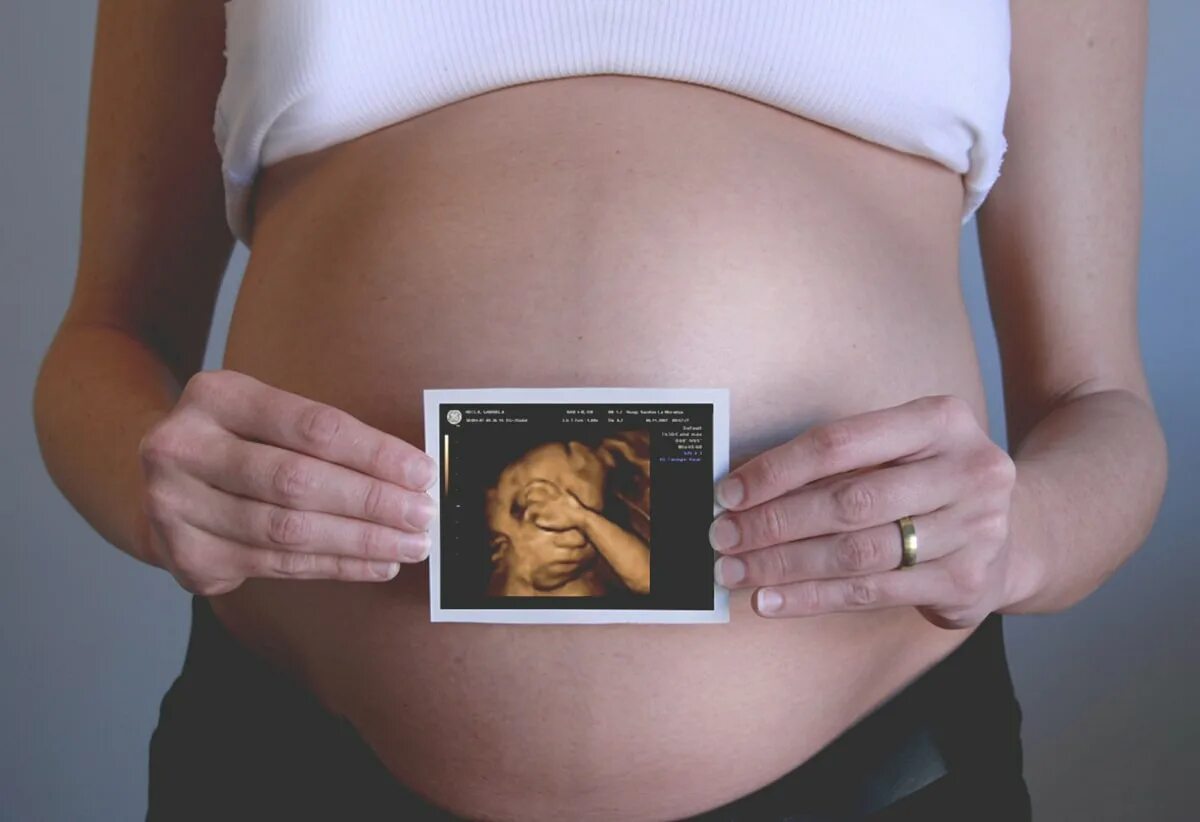

Недели третьего скрининга